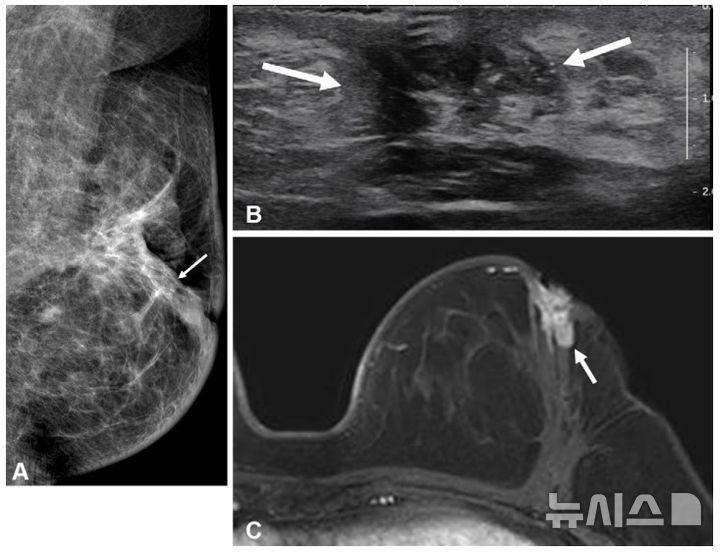

수술 전 MRI 여부에 따른 예후 분석

유방 MRI는 유방암 검사 중 가장 민감도가 높아 유방촬영술과 초음파에서 놓친 종양도 탐지할 수 있다. 그러나 젊은 환자의 수술 전 MRI 검사가 장기적 예후에 미치는 영향, 특히 호르몬 수용체 상태에 따른 영향은 명확히 규명되지 않았다.